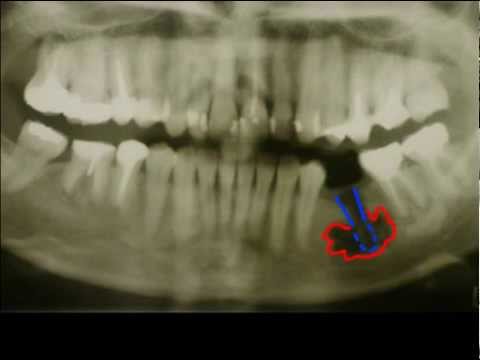

Запущенный кариес, переходящий в пульпит, периодонтит, длительно существующие киста или гранулема зуба могут вызвать воспаление надкостницы – периостит, более известный в народе как флюс. Инфекция распространяется на все компоненты кости - развивается остеомиелит. В ряде случаев воспаление сопровождает отек лица и обусловлено травмой либо заносом микроорганизмов с кровью из других органов, но гораздо чаще источником инфекции является больной зуб. Порой человек и не подозревает, что в плохо залеченных зубных каналах продолжается воспалительный процесс. В тот ноябрьский воскресный день врач-стоматолог Екатерина Козолий уже завершала прием, когда раздался тревожный звонок: пациентка жаловалась на резкую зубную боль, односторонний отек лица, ограничение подвижности челюсти. Хирург-стоматолог Михаил Бородин заочно предположил, что речь про периостит, однако аппаратное исследование показало остеомиелит челюсти и необходимость скорейшего оперативного вмешательства. В сложных случаях при остеомиелите счет идет на часы, объясняют врачи, и оттого, насколько быстро пациент обратился за профессиональной помощью, зависят степень опасности осложнений и нужность / необязательность госпитализации. Наша история закончилась благополучно – подробности в видеосюжете. --------- Вам понравилось видео? Ставьте лайки, пишите отзывы, будьте с нами! ПОДПИСЫВАЙТЕСЬ НА КАНАЛ    / @dentalservice_tv   Дентал ТВ - первый образовательный канал о профилактике и лечении заболеваний полости рта. Наша цель - свести к минимуму стоматологические заболевания. Здесь мы говорим о важных профилактических действиях понятным, доступным языком. Дентал-Сервис это современная стоматология, поэтому мы показываем только современные и актуальных практики лечения, выполняемые нашими стоматологами. Не забудем и про самых маленьких зрителей. Детская стоматология - важная часть нашей работы! Красочные детские сюжеты помогут заинтересовать малыша и научить беречь зубки с раннего детства. --------- ПОДПИШИСЬ НА ДЕНТАЛ ТВ! -